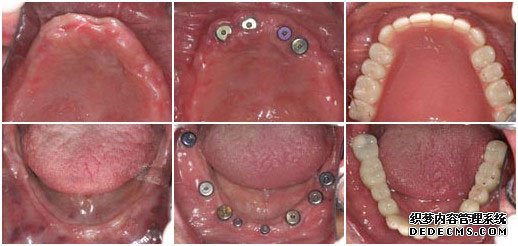

种植牙前                             植入种植体后                   套上烤瓷牙冠完成手术

牙症:全口牙缺失

检查:全口牙齿缺失,无能明显依托的牙根,X片显示根尖无异常

美牙方案:通过口腔数码内窥镜、口腔全景机及微创无痛设备,精密观测口腔内的状况,运用先进的瑞士ITI种植牙技术进行种植。

美牙后:全口牙修复成功,恢复了咀嚼功能,饮食和说话都能自如。

王老伯来武汉爱齿尔口腔就诊的时候,情况非常糟糕,在医生的检查下,发现他口腔内的牙齿全部缺失,并没有可持久依托的牙根,面对这一情况,医生只有建议王老伯做种植牙。虽说种植牙的治疗时间较长,但是对于王老伯这样的牙齿状况,种植牙是一种十分理想的选择。

由于王老伯今年已经61岁,所以在植入种植体后的恢复时间比一般人要常一些,花了将近5个月的时间才长好,但这并不影响种植牙的效果。最后在套烤瓷牙冠的时候,王老伯的家人也感到十分惊异,因为种出来的牙齿不但美观漂亮,甚至比王老伯之前的真牙还要逼真,一下子王老伯的牙齿看起来仿佛只有20多岁。而最最高兴的还是王老伯,他说:“我以前戴的全口活动假牙,吃东西不方便,连老伴弄的饭菜也都不想吃,可这次种牙太成功了,真是那句老话:‘牙好,胃口就好啊!’,太感谢你们了”